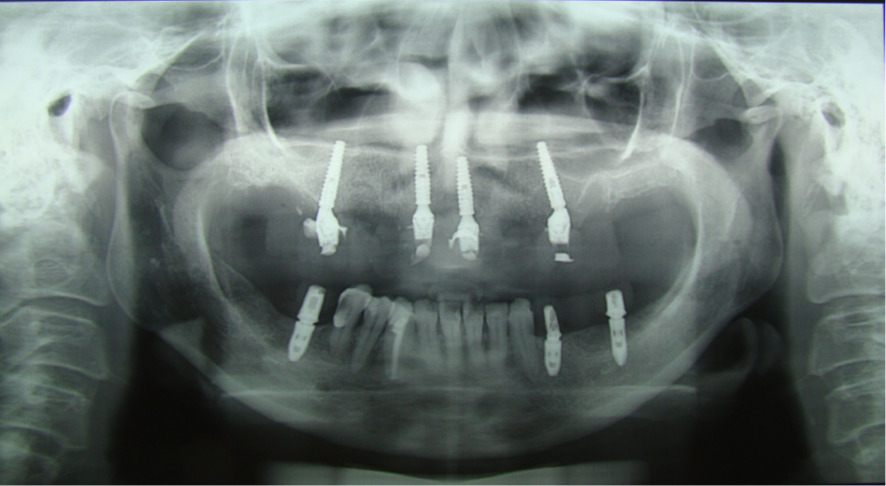

Instalados pilares Mini Cônicos Implacil De Bortoli e coifas de titânio, sendo os gaps alveolares preenchidos com Extra Graft.

Após o período de osseointegração, verificamos que o implante na região do elemento 12 não apresentava tecido mole para o correto perfil de emergência.

Optamos então por substituir o componente protético do elemento 12, de Mini Cônico 4,8 mm de diâmetro e 2,5 mm de cinta gengival, para Micro Cônico 3,5 mm de diâmetro e 1,5 mm de cinta gengival.